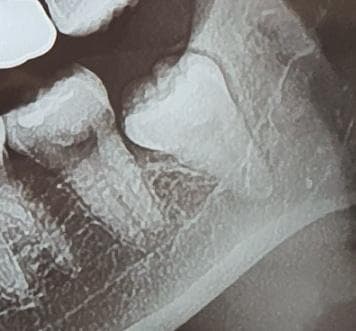

사진으로 보이는 사랑니는 잇몸 안에 완전히 맹출되어 있고 주변 조직에 특별한 문제를 일으키지 않습니다. 따라서 통증을 유발할 가능성은 매우 낮습니다.

해당 부위에 다른 통증의 원인이 있지 않은지 확인해보는 것이 좋습니다. 매우 깊게 매복되어 있는 사랑니기 때문에 일반 병원에서는 발치를 해주지 않을 경우도 있습니다. 이런 경우에는 대학 병원에 구강 외과에서 발치를 하는 것이 좋을 수 있습니다.

저정도 깊이라면 일단 CT를 찍어보셔야될것같습니다. 엑스레이 상으로는 신경관과는 닿아 잇진 않고 신경관 옆으로 치아가 위치한거 같습니다.

위 사진만으로는 명확히 알 수는 없으나 신경이 가까운 부위는 맞기에 대학병원 가시는 게 좋습니다.

뼈 속 깊이 박혀있고, 신경관과도 가까워서 아마 개인치과에서는 대학치과병원이나 사랑니 전문병원 가라 할 것 같습니다. 물론 자신있는 원장은 자기가 뽑아주겠다 할거고요